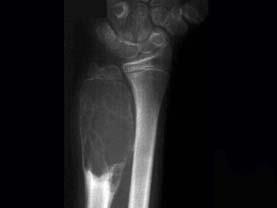

男性,17岁,近2年来感右前臂疼痛,肿胀,2周前由于疼痛加剧,查体右前臂压痛明显,皮肤稍显红肿,请结合所提供图像,选择最佳选项 ( )A、软骨...